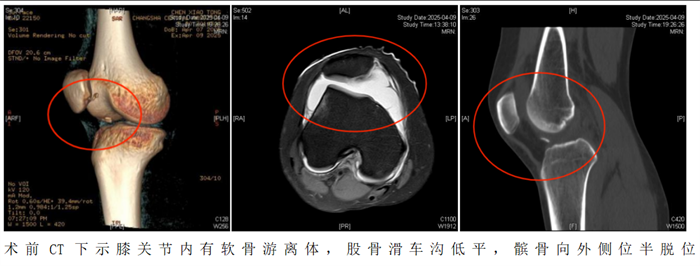

“患者入院后,我们为她制定了周密的个性化治疗方案,采用‘关节镜下髌骨成形术+纽扣十字缝合法软骨修复术’帮助恢复膝关节功能。”据91短视频

(南华大学附属长沙中心医院)运动医学、创伤关节、骨病科主任丑克介绍,这项联合术式在省内少见,因患者游离软骨骨碎片大,软骨下骨骨质有血运,髌骨内下缘软骨缺损面积大,通过高强度缝线采用纽扣十字缝合法原位缝合剥脱的软骨块成形髌骨,犹如为膝关节打造了一个防护网。手术过程顺利,术后患者恢复良好。

2.如果出现以下情况需要考虑手术治疗。初次脱位后出现髌骨或股骨软骨骨折导致关节内出现游离体时,必须手术治疗。关节镜是目前成熟的关节内镜技术,医生通过内镜,直视下观察髌骨的损伤,取出游离体并修复软骨,行内侧支持带紧缩和外侧支持带松解术,即可取得满意的疗效。该手术是微创手术操作,创伤小,恢复快,多数患者术后第1天即可下地活动。